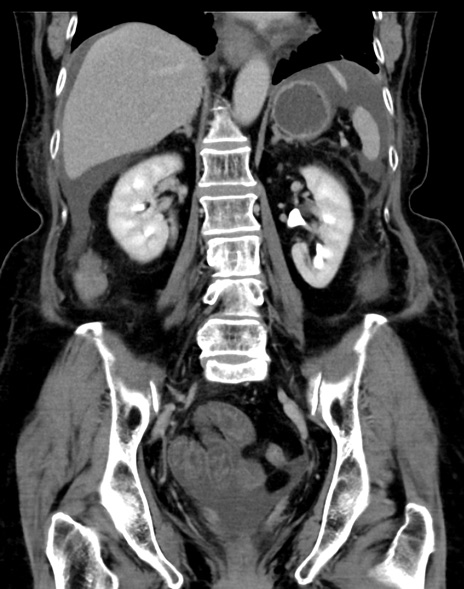

症例13 CT(冠状断像)1日半後